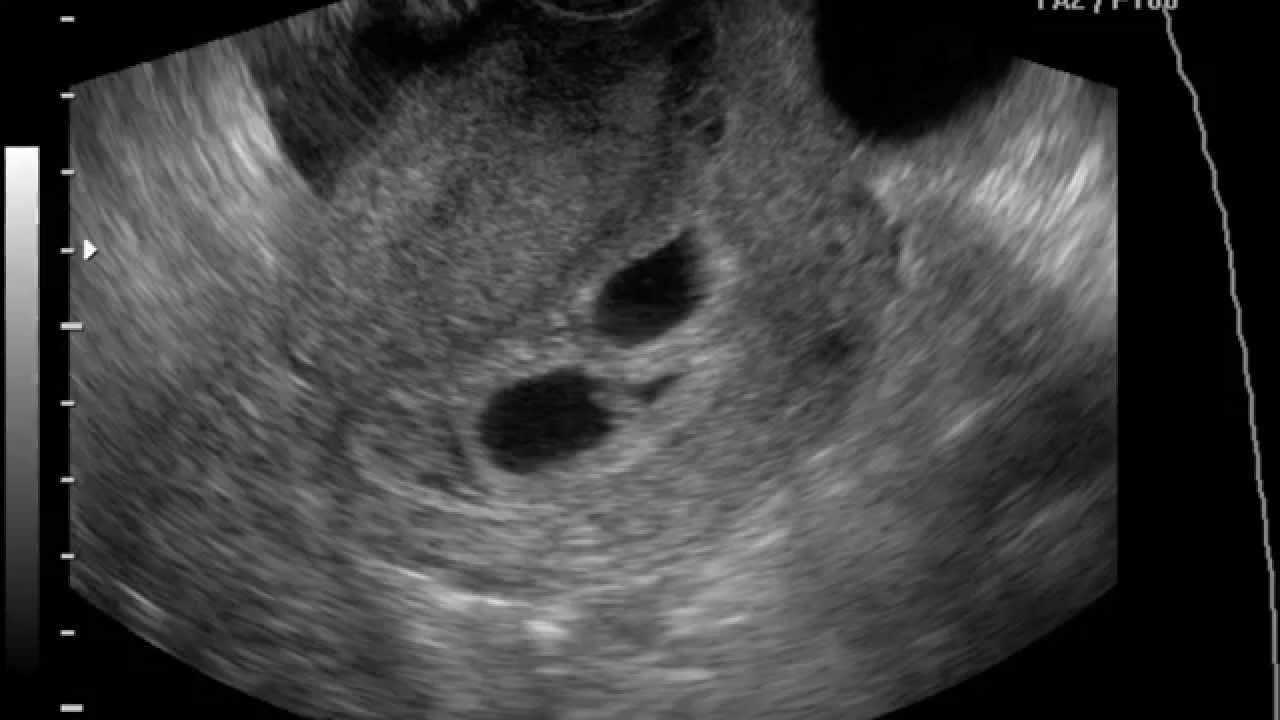

С помощью УЗИ уточняется объём околоплодных вод, вес плода и другие его параметры. По результатам врач сможет определить ИАЖ — индекс амниотической жидкости. Под ним понимают суммарную площадь не занятых плодом и пуповиной мест внутри матки. Именно результаты индекса дают точный ответ, есть ли у беременной многоплодие.